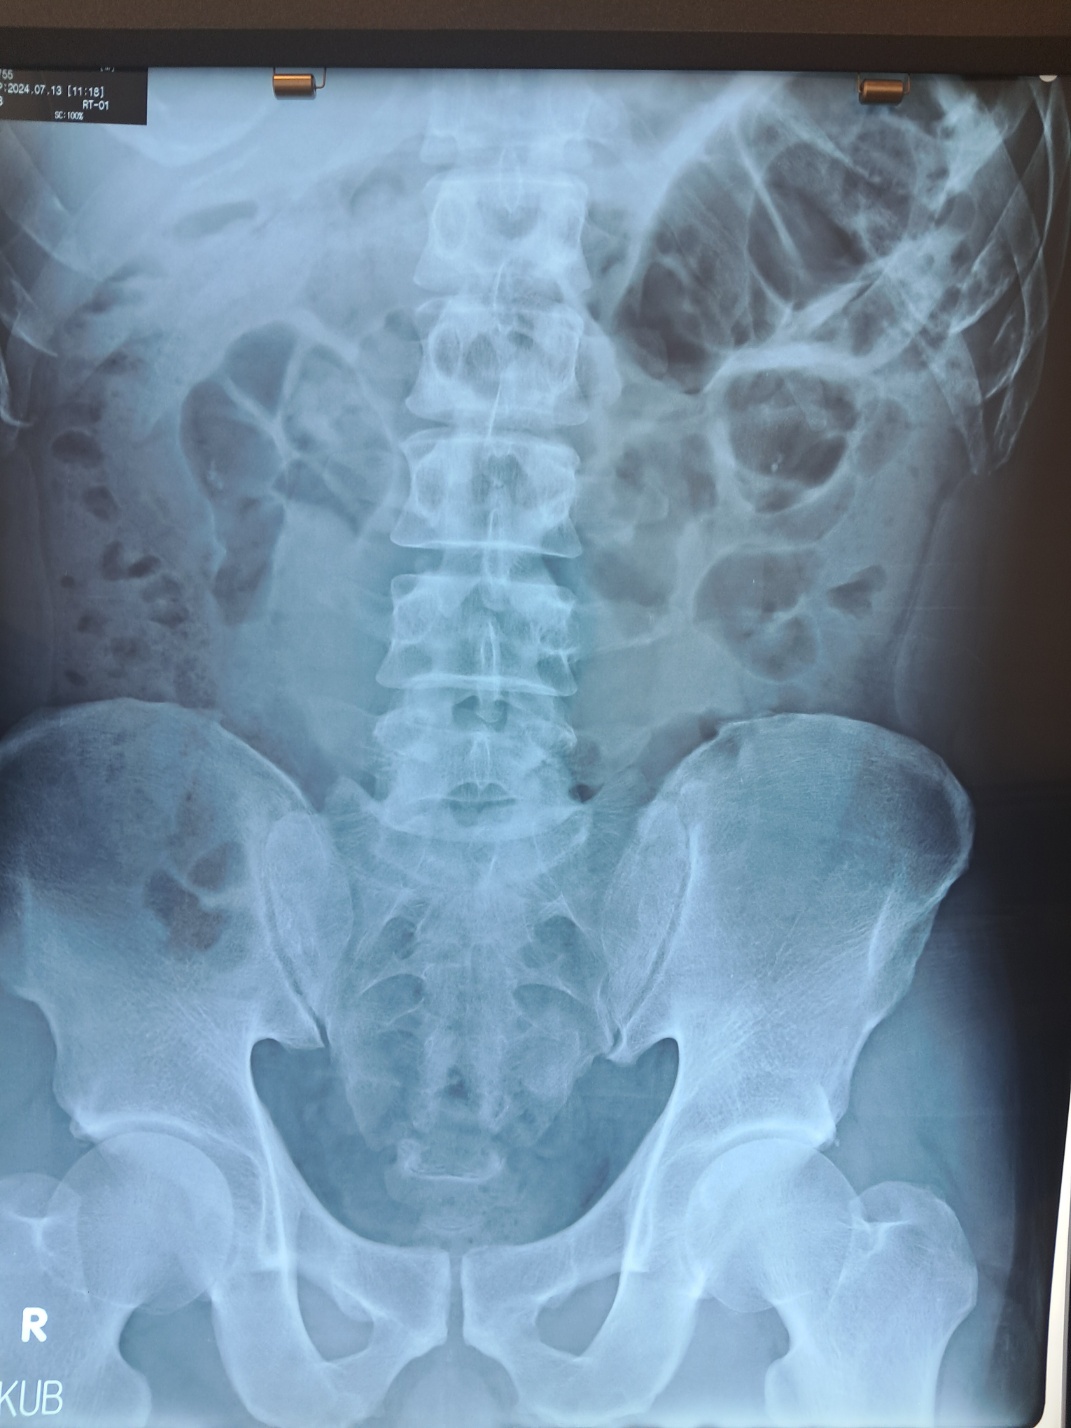

요로결석(尿路結石, Urolithiasis)은 신장, 요관, 방광, 요도 등에 돌(결석)이 생기는 질환입니다. 결석이 소변 배출을 방해하면 극심한 통증이 발생하며, 심한 경우 수술이 필요할 수도 있습니다.